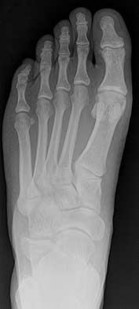

Figures 3a through 3h

A B

C

3

D E F

G

H

1

2

4

- TC posterior facet coalition

Tarsal coalitions occur when primitive mesenchymal cells fail to differentiate and form the

normal articular separations between the tarsal bones of the hindfoot. Overall incidence is difficult to determine because many affected people are minimally symptomatic or asymptomatic. Symptomatic tarsal coalitions typically present in adolescents as a painful flatfoot; however, there are a number of possible presentations, and occasionally symptoms do not appear until adulthood. Most tarsal coalitions are between the calcaneus and the navicular (CN) and the talus and the calcaneus (TC). Although most TC coalitions are across the middle facet, posterior facet coalitions do occur. Plain radiographic evaluation of suspected tarsal coalition is the mainstay for diagnosis. However, coalitions can be bony or fibrous, and making the diagnosis can be difficult. The addition of CT images to distinguish bony definition and MR images to decipher soft tissue can aid in diagnostics. Bony coalitions appear as definite bony bridging between the bones, while fibrous coalitions are suspected when distortion of the bony anatomy is seen. Bony coalitions are best seen on the oblique view (CN) and Harris axial view (TC). There are a number of secondary signs such as the anteater (AE) sign (elongation of the anterior process of the calcaneus as it extends to the navicular as seen on the lateral view [CN]). talar beaking (traction spur of the talar neck thought to result from abnormal stresses as seen on the lateral view [both CN and TN]), and the “C” sign (a continuous cortical contour from the medial talus to the sustentaculum tali [ST]) as seen on the lateral view (TC). A number of newer signs are not as well known, such as a broad mediolateral dimension of the navicular on the anteroposterior (AP) view (the

navicular is wider than the talar head [CN]), nonvisualization of the middle facet on the lateral view (TC), the brick sign (a normal ST is flat, but a distorted ST is enlarged and curved [CN]), and a tapered lateral navicular bone as seen on the AP view (the medial navicular [CN] is much thicker than the lateral navicular).

Figure 3a shows a flatfoot. Figure 3b shows an MF and TB, but not a C sign. Figure 3c shows a bony irregularity between the calcaneus and the navicular and a WN. Figure 3d shows an MF. Figure 3e shows an MF, but narrowing or loss of the posterior facet. Figures 3f through 3h show medial edema and joint irregularities consistent with a posterior facet coalition.